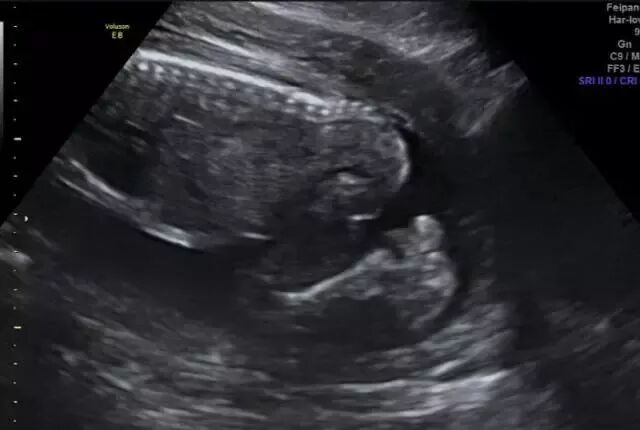

定期做孕期检查

怀孕后立即建立围产保健卡定期检查,11—13周+6天时可做唐氏筛查,20—28周之间做四维彩超等,这些检查都可以在怀孕早期查出胎儿是否畸形。

四维彩超—排畸小助手

目前检查胎儿是否畸形,国际上最通用也是很安全的方式是超声检查。现在国际上这方面最普遍的仪器就是美国GE集团的GE Voluson E8四维彩超仪器,阳泉华康医院作为阳泉专业妇产医院,率先引进美国GE Voluson E8四维彩超设备,为母婴健康保驾护航。

美国GE Voluson E8对胎儿心脏、唇裂、四肢发育异常、脑膜膨出、脊柱裂、腹壁裂等先天性畸形及发育异常能达到最佳的检测效果,为临床诊断提供准确的科学依据。